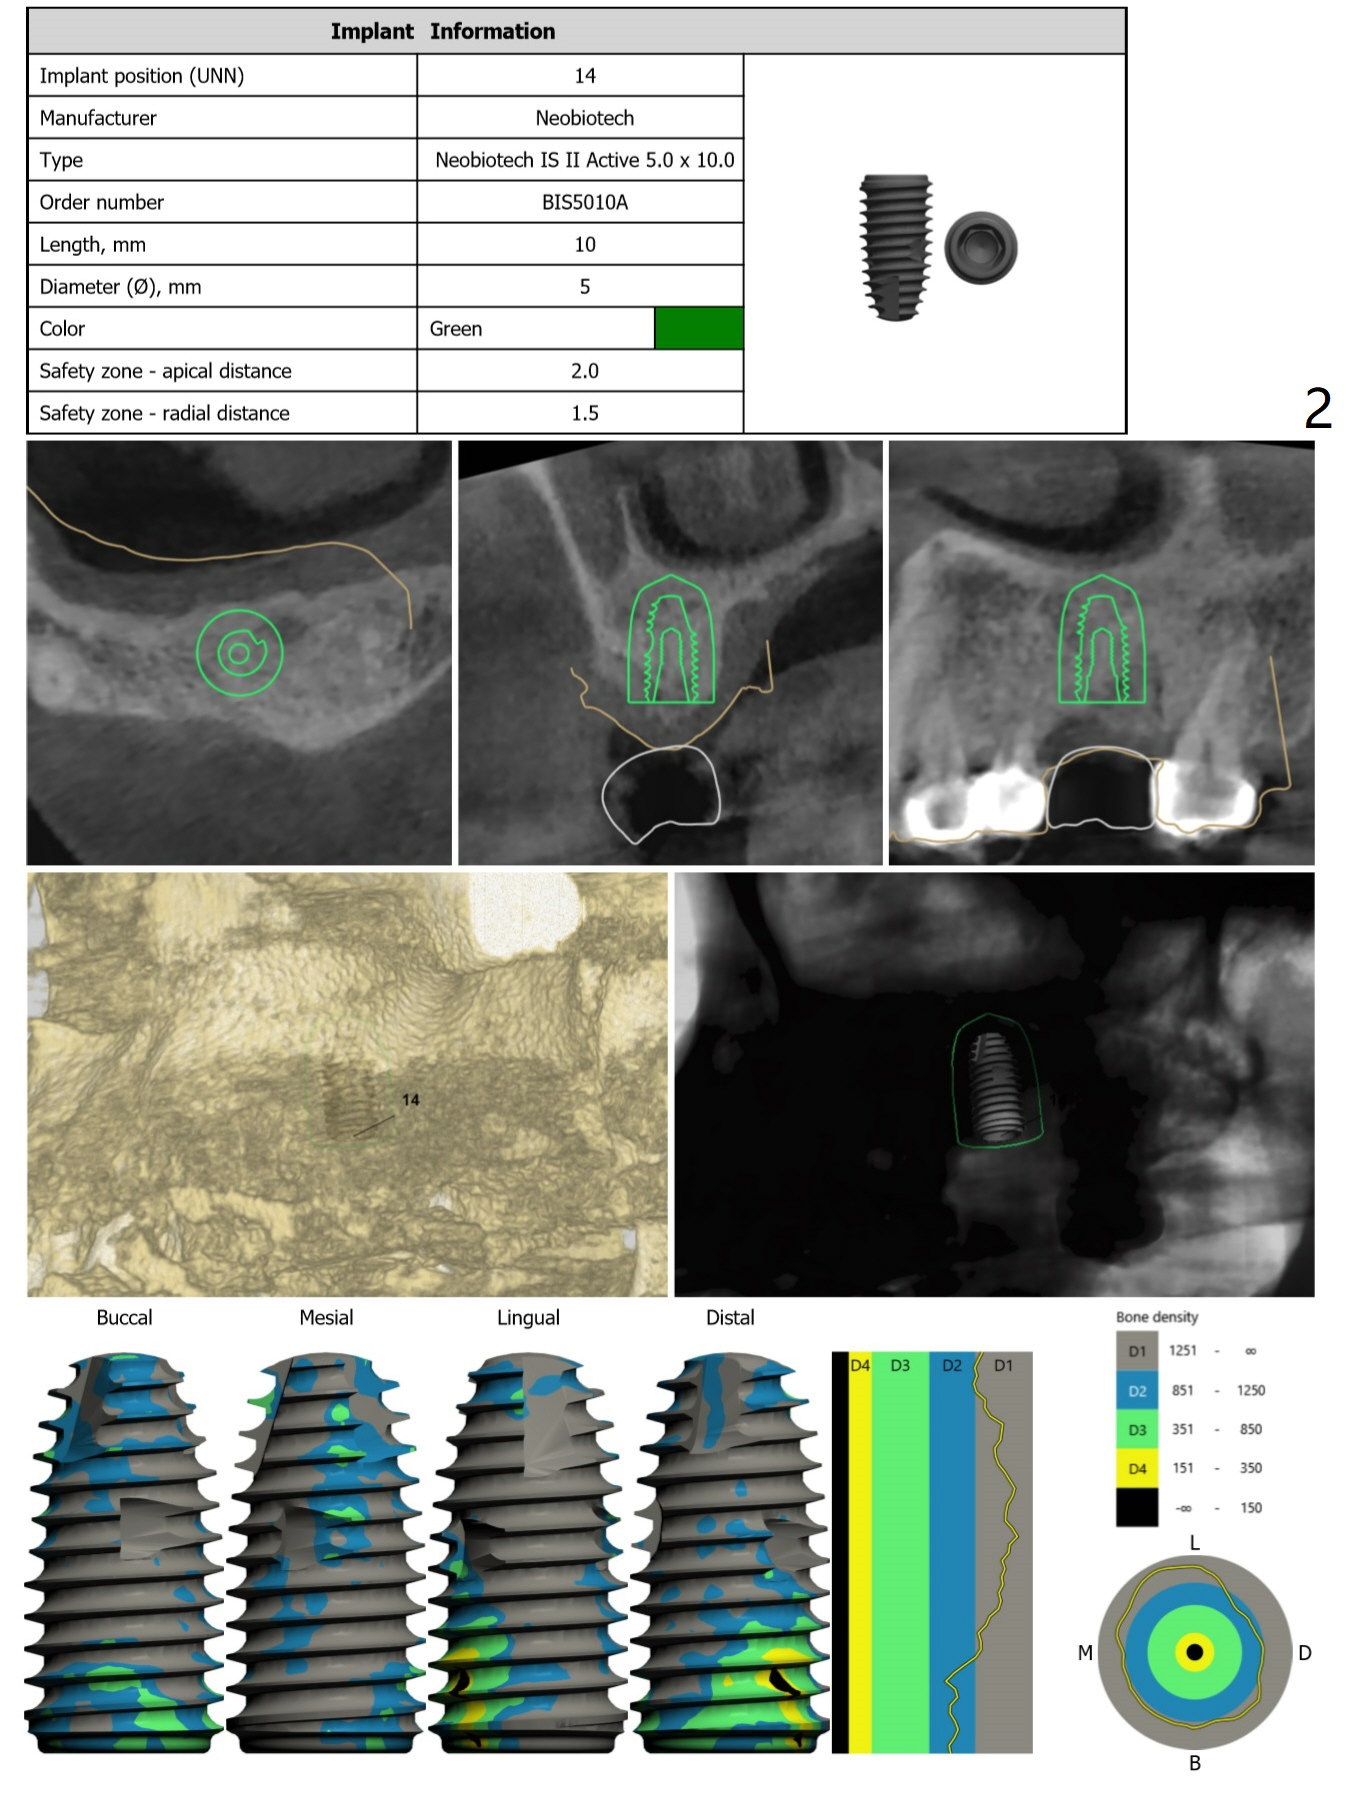

Palatal Placement

Return to Upper Molar Immediate Implant Trajectory II  SP 位点保留后